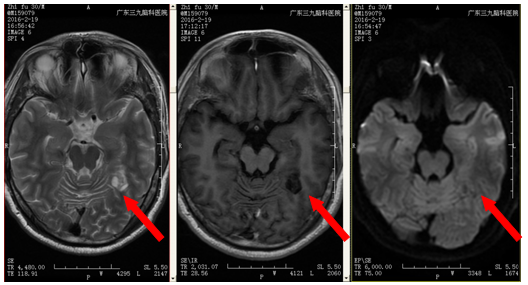

植先生,因3个月前无明显诱因出现四肢抽搐,伴意识障碍,伴抽搐后头痛,遂就诊当地医院,颅MR提示:左侧枕颞叶交界处底部占位性病变,为求进一步治疗来我院就诊,入院后完善相关检查,行左侧枕颞叶交界处占位性病变切除术+ICP探头置入术,术程顺利,病理提示:左侧枕颞叶交界处胚胎发育不良性神经上皮肿瘤(DNT,WHO 1级),术后恢复良好。

术前检查

该病变属于胚胎发育不良性神经上皮瘤(DNT),主要见于青少年,男性患者稍多于女性。DNT主要表现为难治性部分性癫痫发作,少数为复杂部分发作。对于影像学,CT通常表现为皮层内边界清楚的低密度病灶,注药无强化,瘤周无水肿,占位效应不明显。MRI表现:T1表现为低信号,T2表现为高信号的边界清楚的病灶,病变周围无水肿,无明显占位效果,注药后有20%-30%的病变出现轻度局灶性强化。1.对曾经有癫痫大发作、头痛患者要引起警惕,及时去医院检查。2.有局部癫痫发作者,应高度警惕发生本病的可能。DNT只能行手术治疗,预后良好,手术切除后不需要行放疗及化疗。术后病变复发率及低,少数病人可能出现复发及恶变。